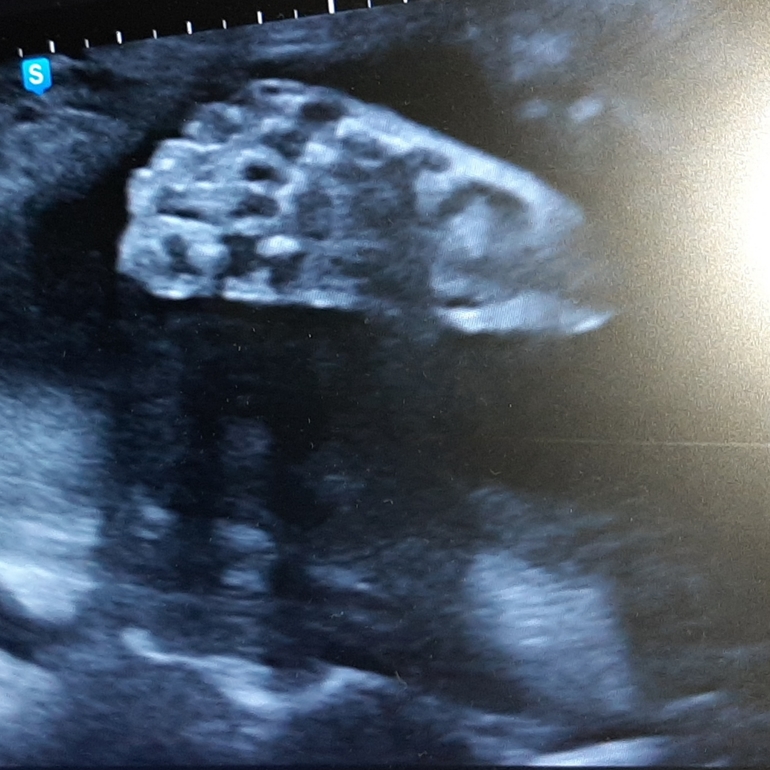

Результаты: УЗИ, КТГ, доплера, скрининга31 неделя, сыну не понравилось, что его рассматривают ...

Крыска